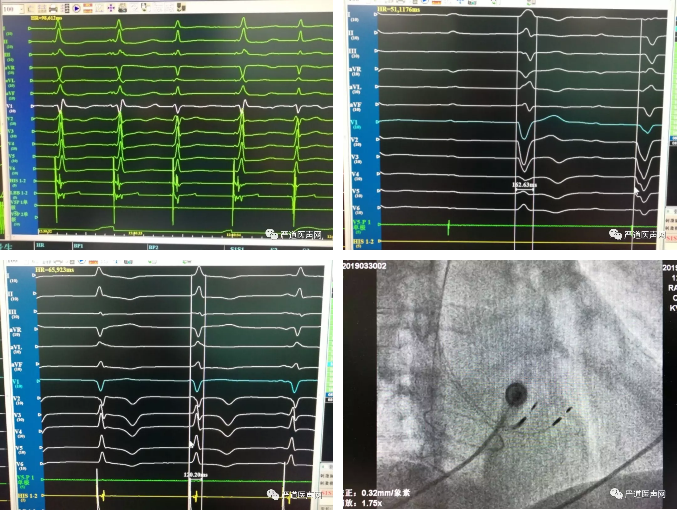

手术演示

在充分了解了4例患者的基本情况之后,焦点转至导管室。李新华主任边手术演示边进行经验分享,悉心回答学员的每个问题,4例手术均成功完成,学员零距离学习了左束支区域起搏的技术方法,针对手术相关细节进行了激烈讨论,同时不断拍照及记录笔记,收获满满,都对此有了更直观更深刻全面的认识。